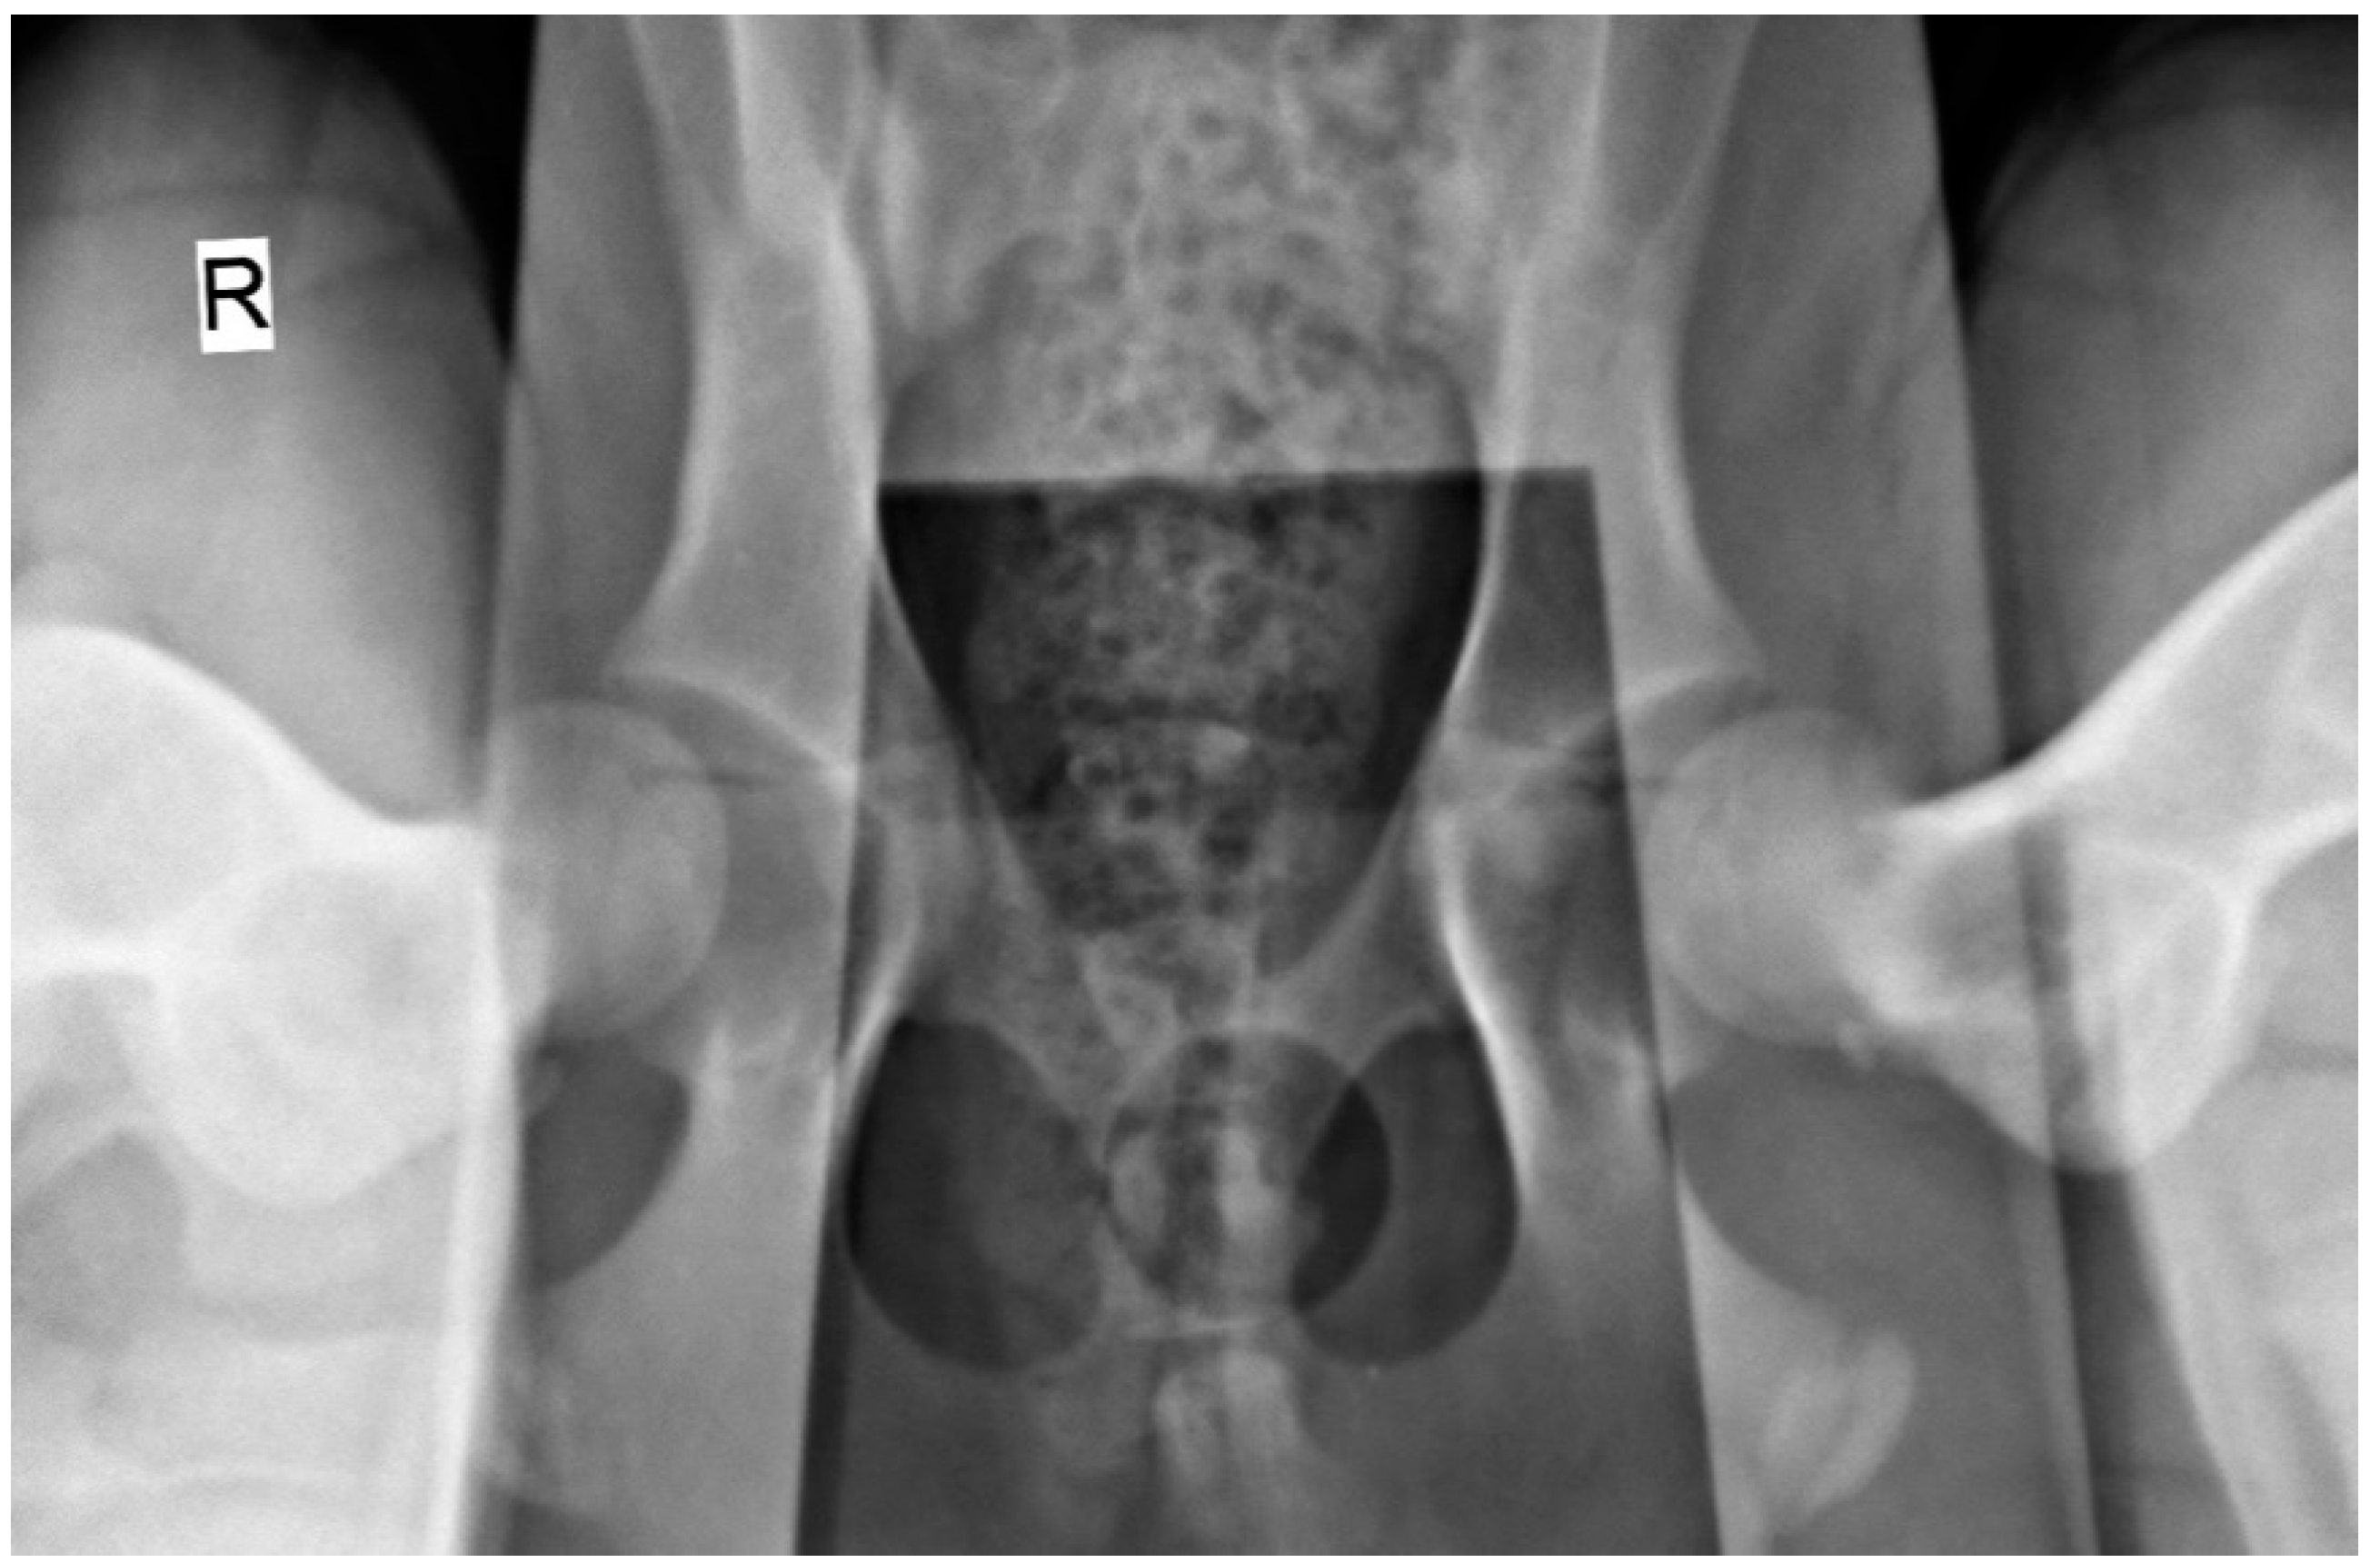

2.2. Radiographic Hip Stress View and Hip Laxity Measurement

2.3. Ultrasonographic Ventral Hip Joint Approach